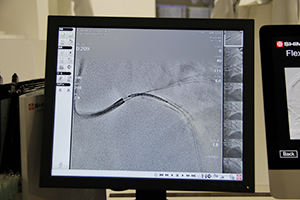

新開発の“SCORE StentShot”※は,経皮的冠動脈形成術(PCI)においてリアルタイムにステント形状確認を支援するソフトウエア。近年,ステントグラフトの細径化が進み,血管内で拡張したステントが視認しにくいことが課題となっている。そこで,新しいリアルタイム画像処理技術を開発し,X線照射量を従来と変えずに,画像ノイズを約50%低減することを可能にした。視認性が向上し,ステントの形状を確認しやすくなることで,安全性の向上と検査時間短縮による被ばく低減に貢献する。

同じく新開発の“Flex-APS”(Flexible Active Pixel Shift)※は,DSA画像のアーチファクトをリアルタイムに自動補正する技術である。造影剤が頭部や下肢に流入すると,被検者が違和感を感じて動いてしまうことがあり,造影前後の位置ズレによりサブトラクション画像にアーチファクトが発生する。Flex-APSでは,動いた方向や移動量をピクセル単位でとらえることで,画像全体を線形補正する方法と比べ,精度の高い補正が可能になる。位置ズレが画像の一部だけであれば,その部分のみを補正し,また,ねじれのような三次元的な動きであっても,非線形に補正することができ,頭部や下肢の明瞭な血管画像を得ることができる。

拍動で動くステントをリアルタイムに固定表示し,ステントポジショニングの確認を支援する“SCORE StentView”には,ステントの視認性をより向上させる改良が加えられた※。従来,SCORE StentViewの画面は,リアルタイム画像,ステント強調画像,ステント検出画像に3分割されていたが,手技で最も重要なステント強調画像の1画面表示に変更し,ステントの視認性をいっそう向上させた。※いずれもW.I.P.

低侵襲がコンセプトの血管撮影装置 |

DSAのアーチファクトを自動補正する“Flex-APS”(W.I.P.) |

1画面表示となった新“SCORE StentView”(W.I.P.) |